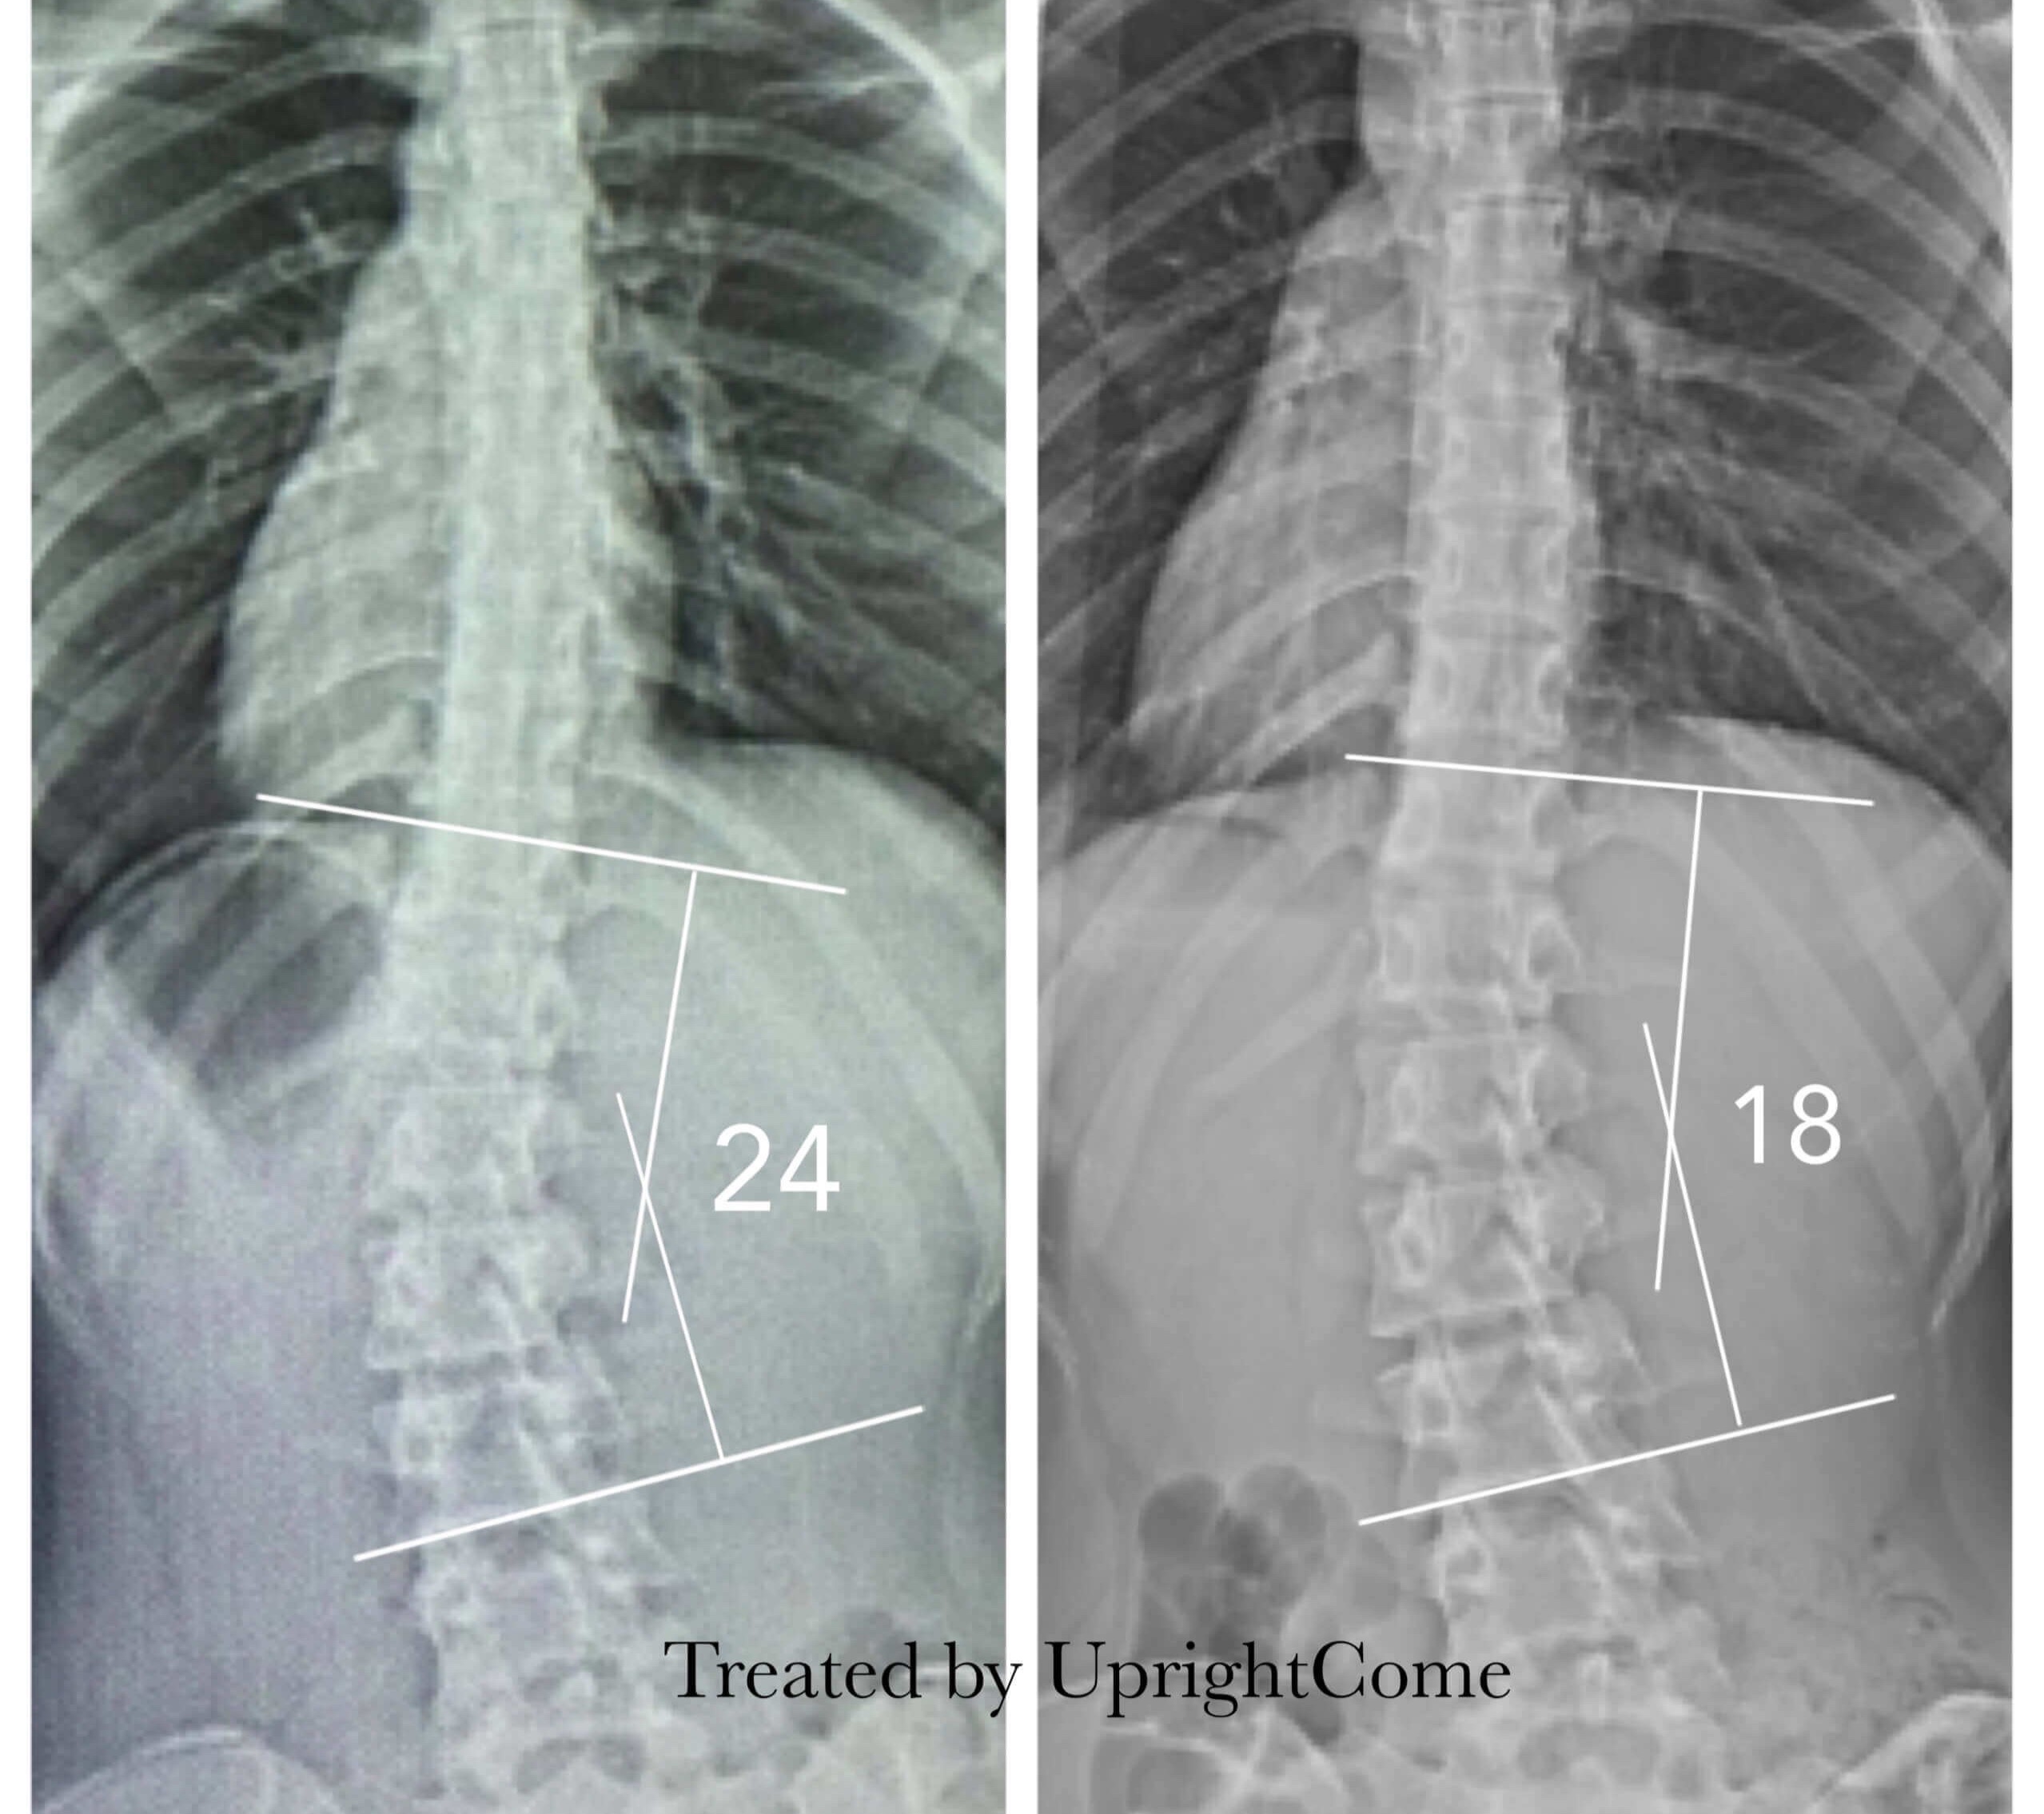

Case 11, 16 years,24° Cobb

![脊椎側彎患者經過側彎矯正治療後,腰椎側彎角度由24度減少到18度。]()